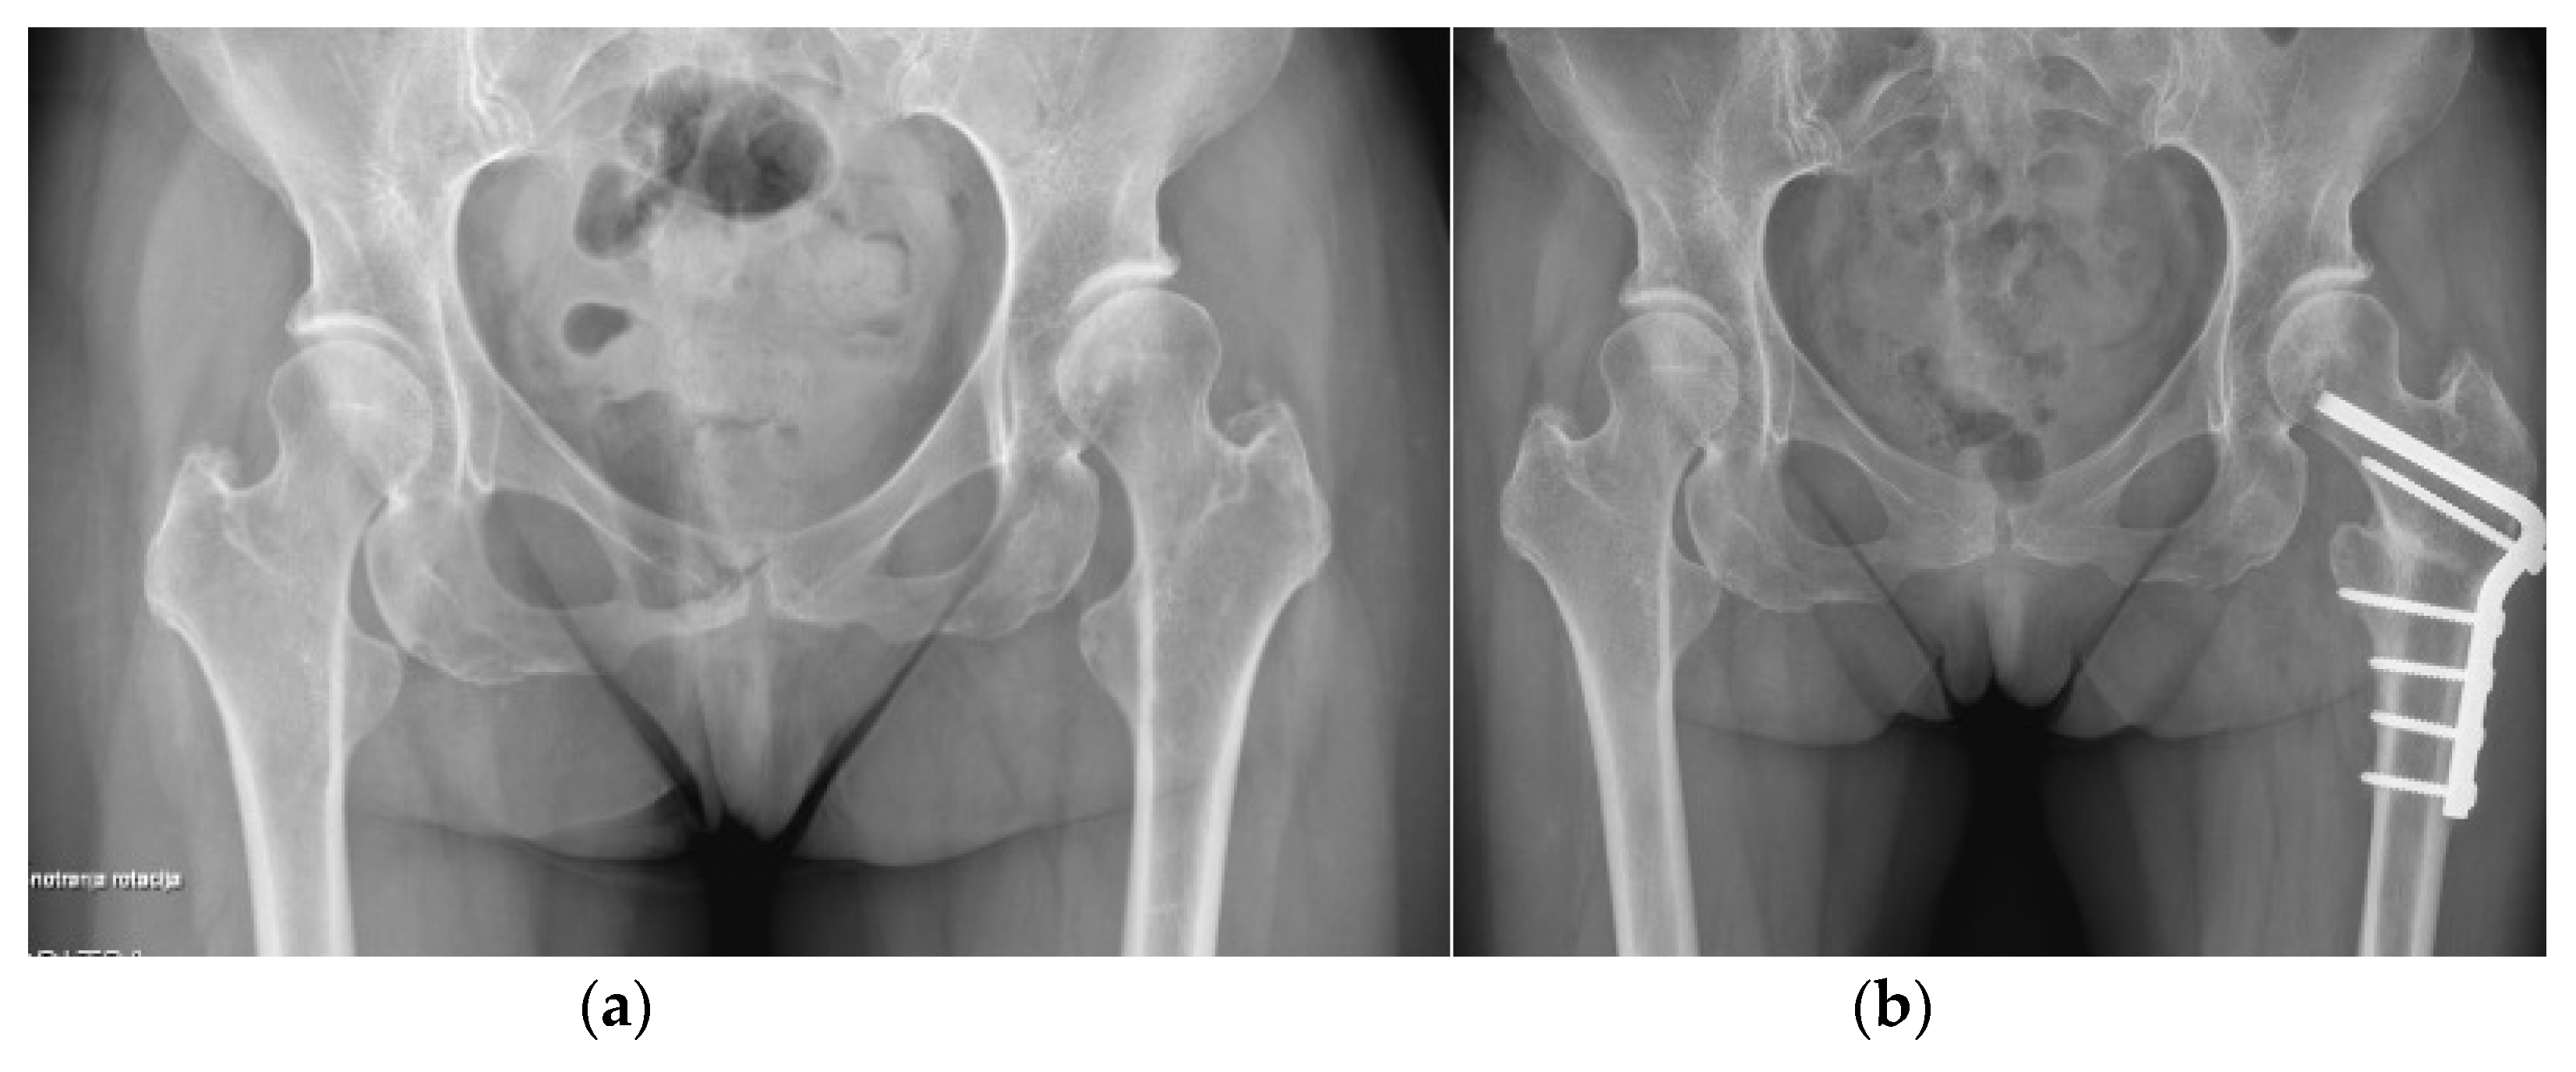

3.5. Hip

- Brumat, P.; Mihalič, R.; Kovač, S.; Trebše, R. Acute Femoral Lengthening in Adults Using Step-Cut Osteotomy, Traction Table, and Proximal Femoral Locking Plate Fixation: Surgical Technique and Report of Three Cases. Indian J. Orthop. 2022, 56, 559–565. [Google Scholar] [CrossRef]